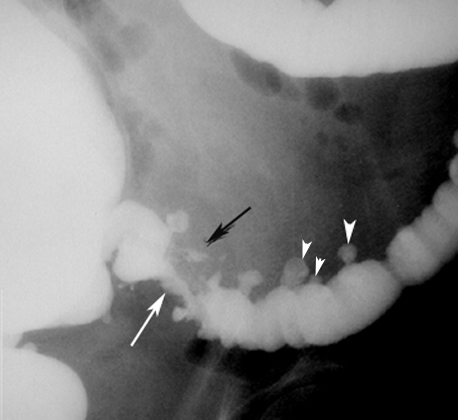

DiverticulaCT: Arrowheads point to multiple diverticula arising from the recto sigmoid. The contrast in diverticula is left over from previously administered GI contrast.

Lower GI showing Diverticula |